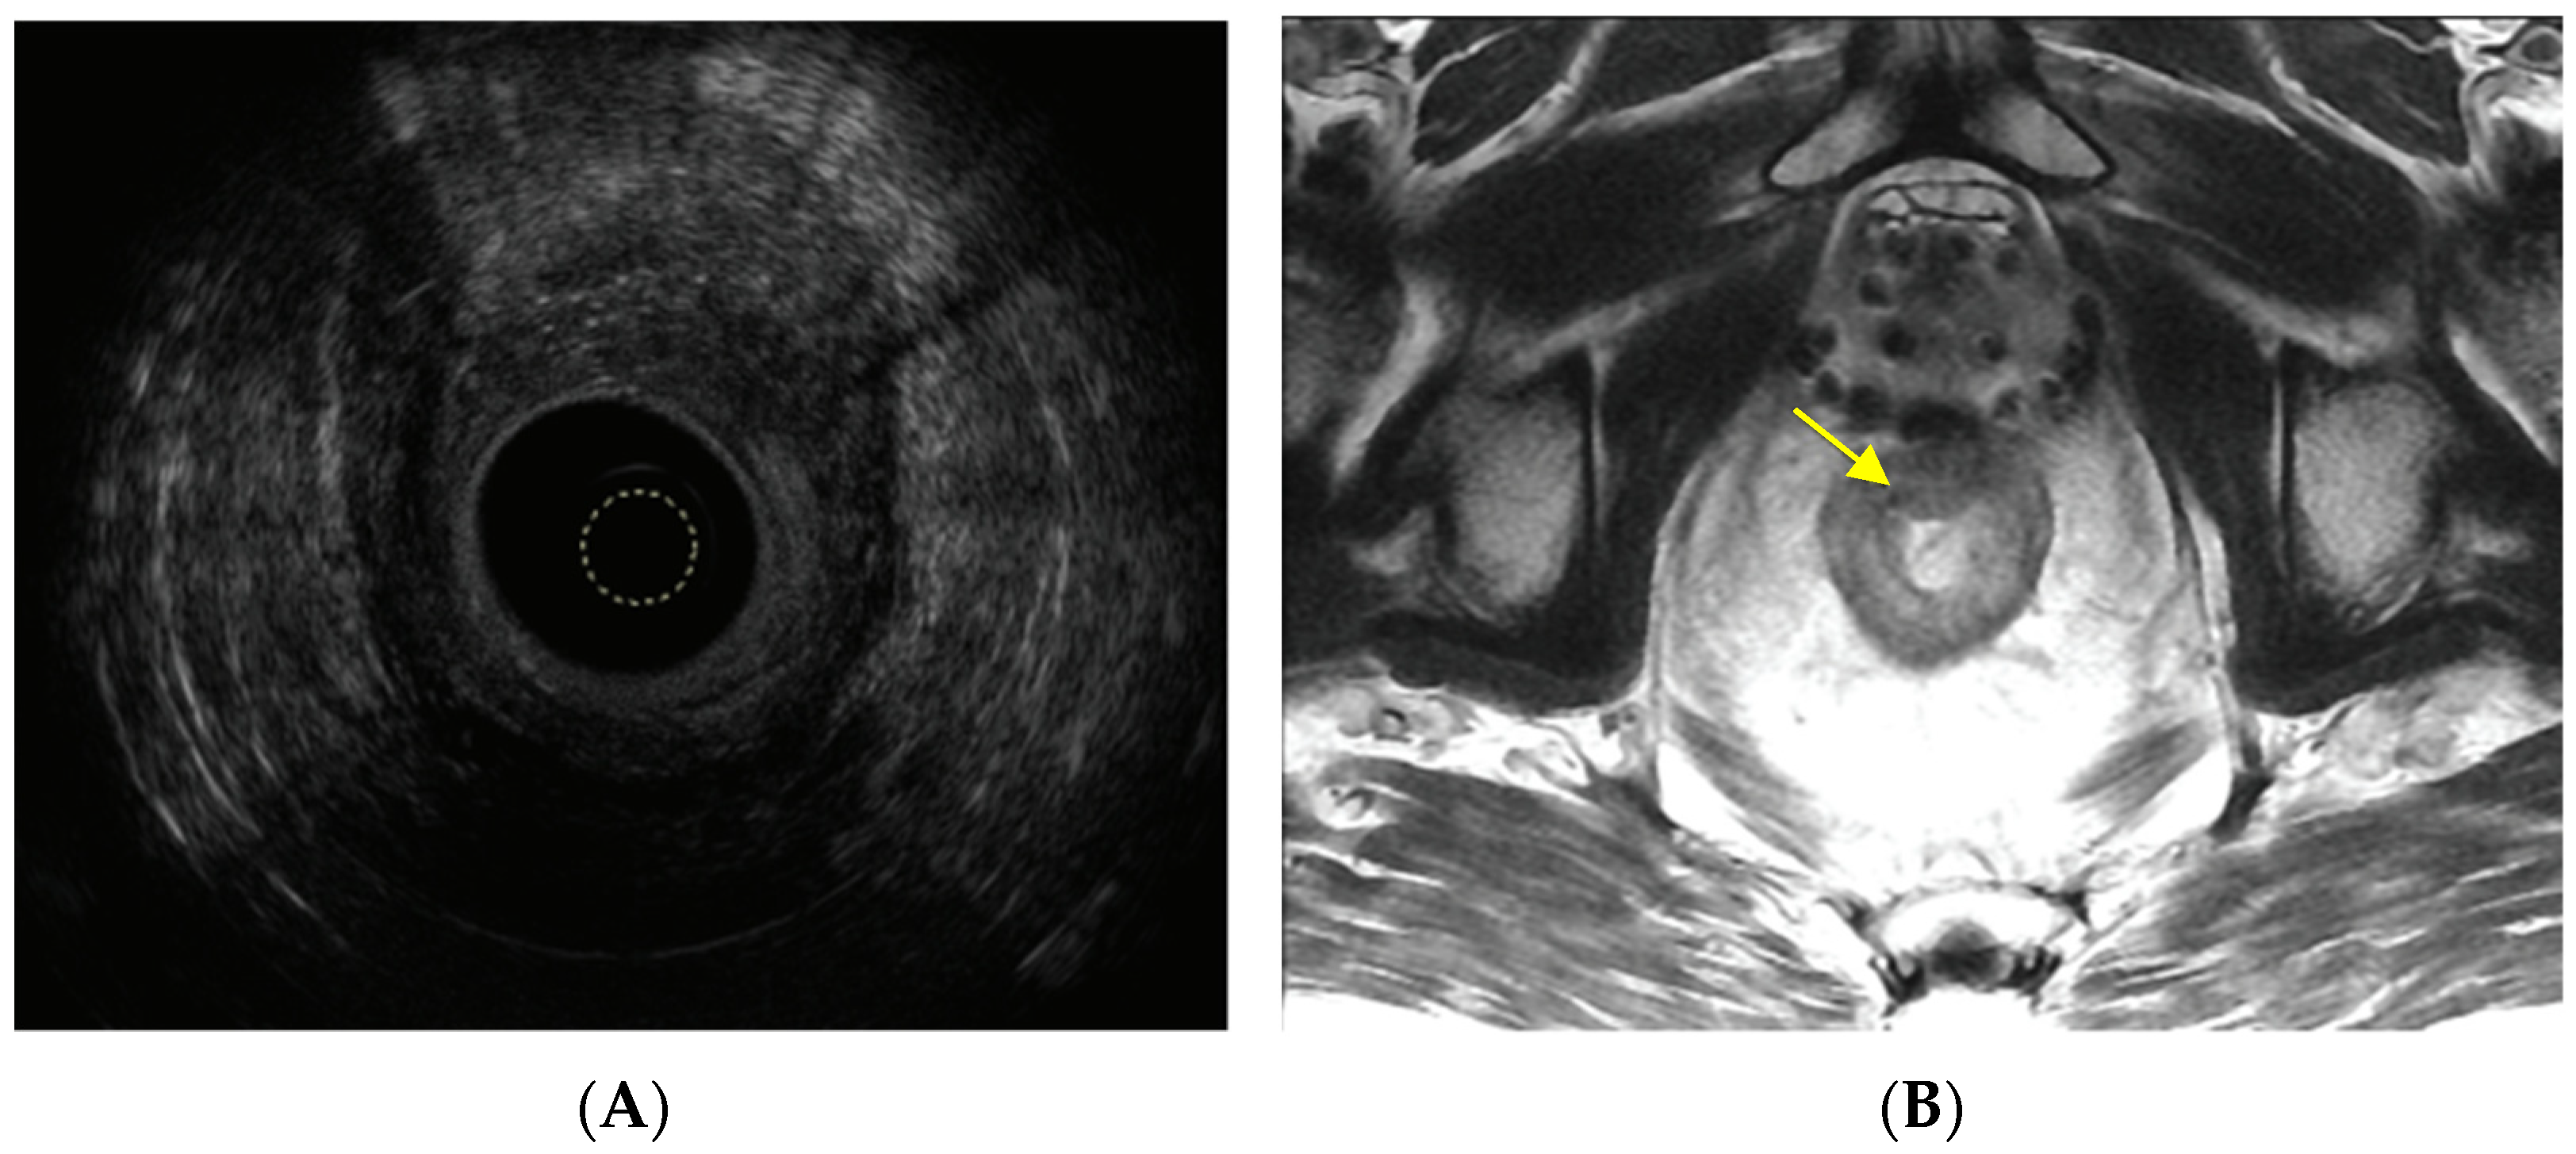

3. Direct Beam Radiation Damages Surrounding Organs

6. Assessment, Surveillance and Diagnosis

- Moreno, C.C.; Sullivan, P.S.; Mittal, P.K. MRI evaluation of rectal cancer: Staging and restaging. Curr. Probl. Diagn. Radiol. 2017, 46, 234–241. [Google Scholar] [CrossRef]